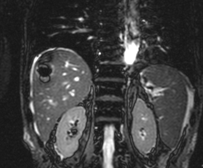

Abdominal CT scan. Hemorrhagic rupture of a simple hepatic cyst without active hemorrhage. The presence of free intraperitoneal fluid is noted (Courtesy Dr. V. Penopoulos)